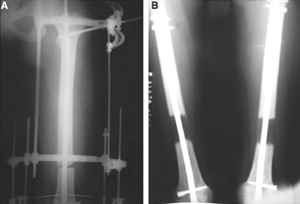

И тракцию бедра на стержне. Типа (СМ картинки).

После выращивания регенерата стержень блокировать.

Если у Вас возникнут какие-то сомнения, то возможно наложение гибридного циркулярного-монолатерального дистракционного аппарата на левое бедро и выполнение остеотомии в в/3 бедра. Почему монолатеральный гибридный аппарат, а не аппарат Илизарова? Эта конструкция гораздо легче переносится пациентами, в ней гораздо удобнее проводить местное лечение ран.

Разрешите рассказать о пациенте, которому мы фиксировали перелом такой конструкцией.

Больной 19 ти лет, пострадал в результате ДТП, пассажир мотоцикла. Получил открытый оскольчатый перелом н/3 левой бедренной кости 3a тип по Гастилло-Андерсену. При поступлении ПХО ран, фиксация стержневым аппаратом наружной фиксации. Лечение больного осложнилось развитием анаэробной флегмоны левого бедра. Лампасные разрезы, неоднократные некрэктомии, некротизировался участок диафиза левой бедренной кости на протяжении 15 см. Произведена резекция. 20.05.10- демонтаж АНФ, остеоситез левой бедренной кости гибридным циркулярно-монолатеральным стержневым дистракционным аппаратом наружной фиксации, остетомия левой бедренной кости в в/3. Сейчас начата дистракция в аппарате, проводится подготовка ран к аутодермопастике.